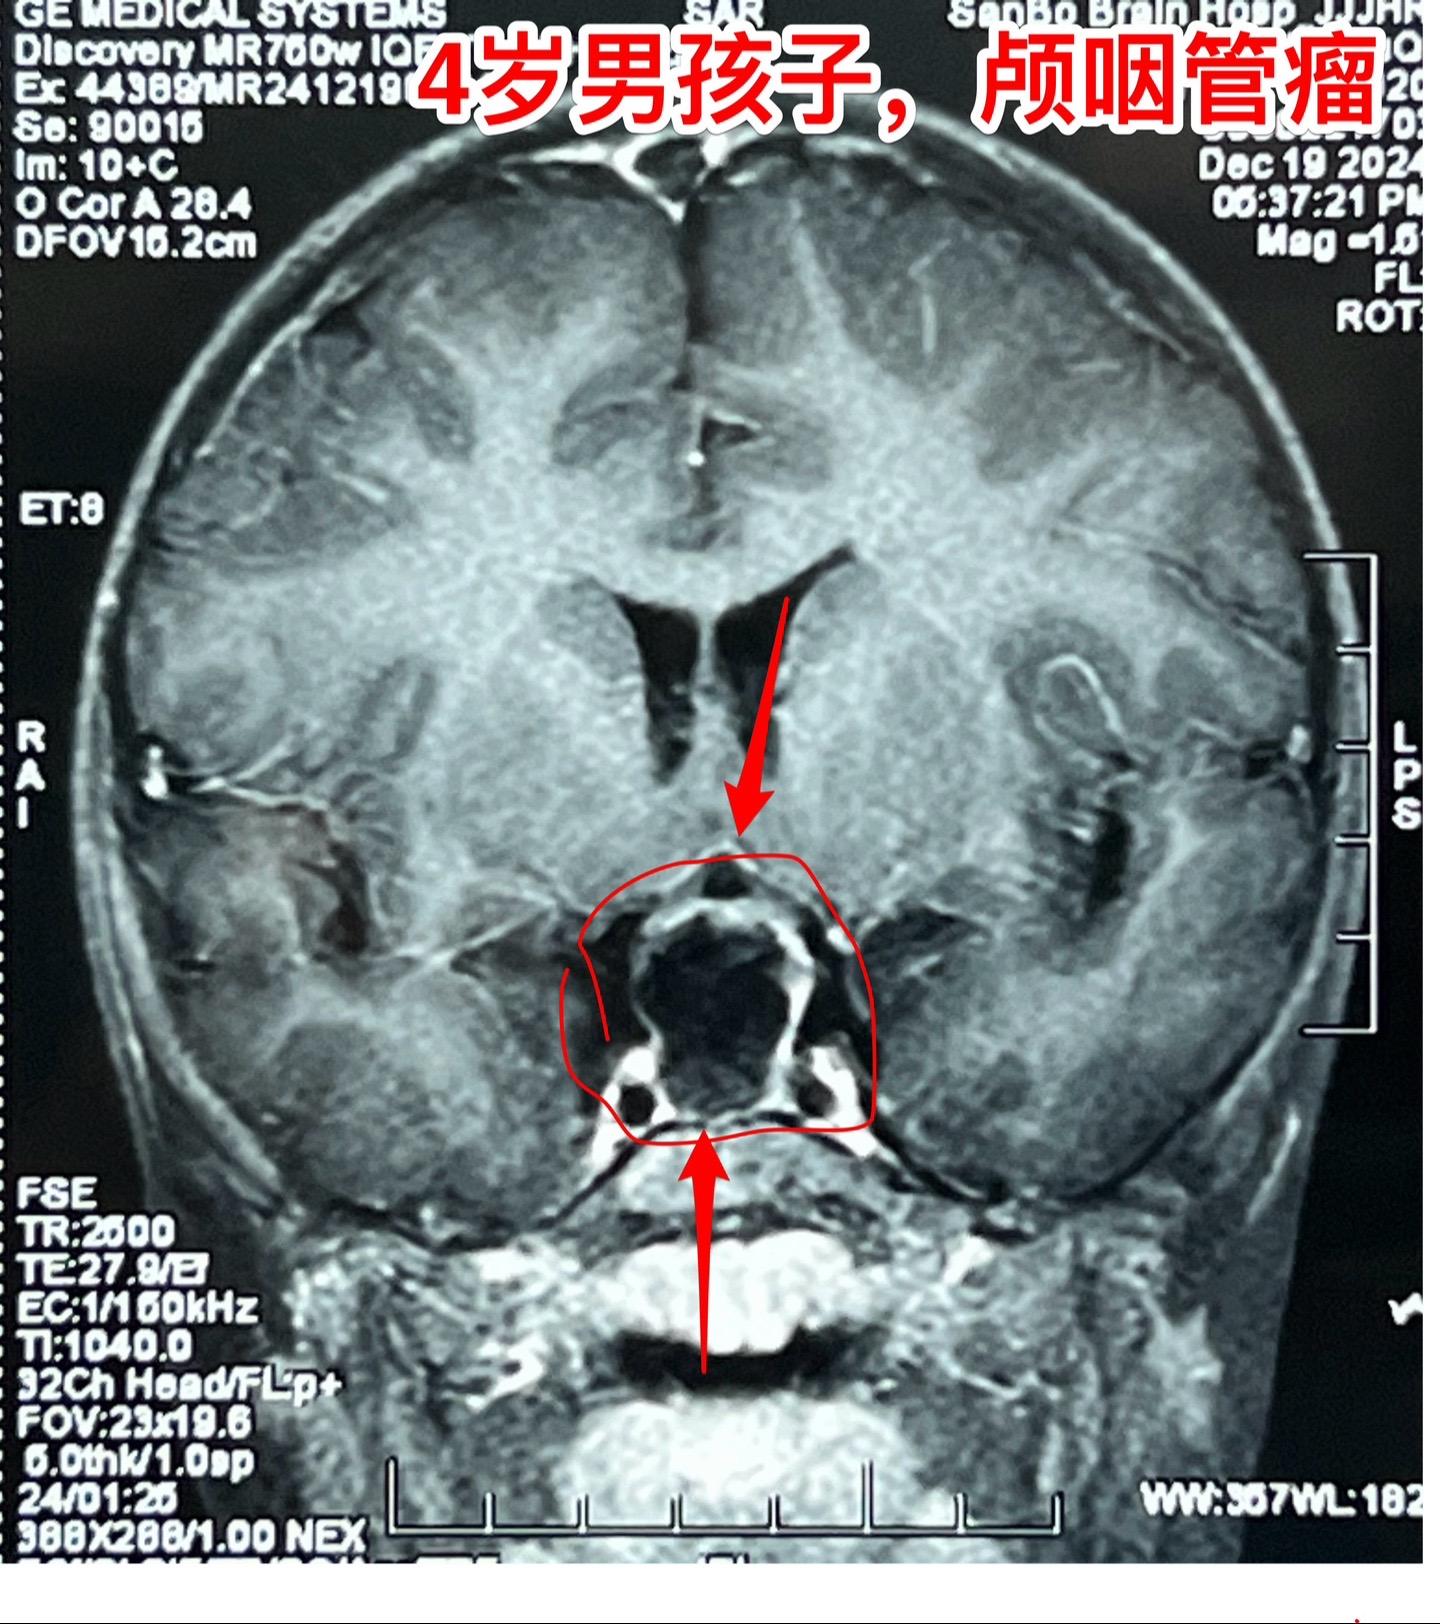

12月26日两个颅咽管瘤手术。第一个四岁男孩子,因为头部受伤,作CT发现颅咽管瘤。家长没有犹豫,选择尽快作手术。手术中将颅咽管瘤完全切除,垂体柄和垂体保留约50%。早作手术的好处就是肿瘤与周围结构粘连不紧密,易于分离,有助于完全切除肿瘤。 第二个病人是14岁男孩子,颅咽管瘤手术后6年,术后半年就发现了肿瘤复发,随后观察,多次复查磁共振显示肿瘤在长大。这个瘤也是在垂体窝内,和第一个病人一样,但是肿瘤与周围结构粘连紧密,切除的难度更大,也得到了完全切除。